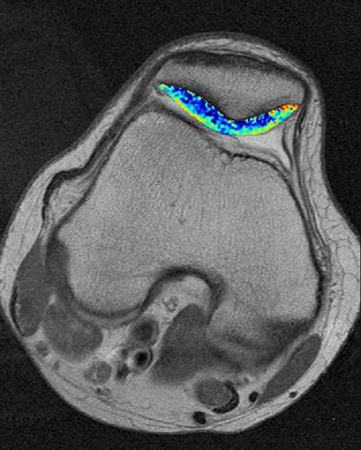

Introduction Spectrum of disease entities from single, focal defects to advanced degenerative disease of articular (hyaline) cartilage Epidemiology incidence 5-10% of people > 40 years old have high grade chondral lesions location chronic ACL tear anterior aspect of lateral femoral chondyle and posterolateral tibial plateau osteochondritis dissecans 70% of lesions found in posterolateral aspect of medial femoral condyle Pathophysiology mechanism of injury acute trauma or chronic repetitive overload impaction resulting in cartilage softening; fissuring; flap tears; or delamination the cause of OCD is unknown pathomechanics impaction forces greater than 24 MPa will disrupt normal cartilage cellular biology cartilage injuries have limited spontaneous healing and propensity to worsen over time Anatomy See Articular Cartilage Basic Science Classification Outerbridge Arthroscopic Grading System Grade 0 Normal cartilage Grade I Softening and swelling Grade II Superficial fissures Grade III Deep fissures, without exposed bone Grade IV Exposed subchondral bone ICRS (International Cartilage Repair Society) Grading System Grade 0 Normal cartilage Grade 1 Nearly normal (superficial lesions) Grade 2 Abnormal (lesions extend < 50% of cartilage depth) Grade 3 Severely abnormal (>50% of cartilage depth) Grade 4 Severely abnormal (through the subchondral bone) Presentation History commonly present with history of precipitating trauma some defects found incidentally on MRI or arthroscopy Symptoms asymptomatic vs. localized knee pain may complain of effusion, motion deficits, mechanical symptoms (e.g., catching, instability) Physical exam inspection look for background factors that predispose to the formation of articular defects joint laxity malalignment compartment overload motion assess range of motion, ligamentous stability, gait Imaging Radiographs indications used to rule out arthritis, bony defects, and check alignment recommended views standing AP, lateral, merchant views optional views semiflexed 45 deg PA views most sensitive for early joint space narrowing long-leg alignment views determine the mechanical axis CT scan indications better evaluation of bone loss findings used to measure TT-TG when evaluating the patello-femoral joint MRI indication most sensitive for evaluating focal defects views Fat-suppressed T2, proton density, T2 fast spin-echo (FSE) offer improved sensitivity and specificity over standard sequences dGEMRIC (delayed gadolinium-enhanced MRI for cartilage) and T2-mapping are evolving techniques to evaluate cartilage defects and repair Studies Laboratory may be used to rule out inflammatory disease Treatment Nonoperative rest, NSAIDs, physiotherapy, weight loss indications first line of treatment when symptoms are mild viscosupplementatoin, corticosteroid injections, unloader brace indications controversial may provide symptomatic relief but healing of defect is unlikely Operative debridement/chondroplasty vs. reconstruction techniques indications failure of nonoperative management acute osteochondral fractures resulting in full-thickness loss of cartilage technique treatment is individualized, there is no one best technique for all defects decision-making algorithm is based on several factors patient factors age skeletal maturity low vs. high demand activities ability to tolerate extended rehabilitation defect factors size of defect location contained vs. uncontained presence or absence of subchondral bone involvement basic algorithm (may vary depending on published data) femoral condyle defect correct malaligment, ligament instability, meniscal deficiency measure size < 4 cm2 = microfracture or osteochondral autograft transfer (pallative if older/low demand) > 4 cm2 = osteochondral allograft transplantation or autologous chondrocyte implantation patellofemoral defect address patellofemoral maltracking and malalignment measure size < 4 cm2 = microfracture or osteochondral autograft transfer > 4 cm2 = autologous chondrocyte implantation (microfracture if older/low demand) Surgical Techniques Debridement / Chondroplasty overview goal is to debride loose flaps of cartilage removal of loose chondral fragments may relieve mechanical symptoms short-term benefit in 50-70% of patients benefits include simple arthroscopic procedure, faster rehabilitation limitations problem is exposed subchondral bone or layers of injured cartilage unknown natural history of progression after treatment Fixation of Unstable Fragments overview need osteochondral fragment with adequate subchondral bone technique debride underlying nonviable tissue consider drilling subchondral bone or adding local bone graft fix with absorbable or nonabsorbable screws or devices benefits best results for unstable osteochondritis dissecans (OCD) fragments in patients with open physis limitations lower healing rates in skeletally mature patients nonabsorbable fixation (headless screws) should be removed at 3-6 months Marrow Stimulation Techniques overview goal is to allow access of marrow elements into defect to stimulate the formation of reparative tissue includes microfracture, abrasion chondroplasty, osteochondral drilling microfracture technique defect is prepared with stable vertical walls and the calcified cartilage layer is removed awls are used to make multiple perforations through the subchondral bone 3 - 4 mm apart protected weight bearing and continuous passive motion (CPM) are used while mesenchymal stem cells mature into mainly fibrocartilage benefits include cost-effectiveness, single-stage, arthroscopic best results for acute, contained cartilage lesions less than 2 cm x 2cm limitations poor results for larger defects >2 cm x 2cm does not address bone defects requires limitation of weight bearing for 6 - 8 weeks Osteochondral autograft / Mosaicplasty overview goal is to replace a cartilage defect in a high weight bearing area with normal autologous cartilage and bone plug(s) from a lower weight bearing area chondrocytes remain viable, bone graft is incorporated into subchondral bone and overlying cartilage layer heals. technique a recipient socket is drilled at the site of the defect a single or multiple small cylinders of normal articular cartilage with underlying bone are cored out from lesser weight bearing areas (periphery of trochlea or notch) plugs are then press-fit into the defect limitations size constraints and donor site morbidity limit usage of this technique matching the size and radius of curvature of cartilage defect is difficult fixation strength of graft initially decreases with initial healing response weight bearing should be delayed 3 months benefits include autologous tissue, cost-effectiveness, single-stage, may be performed arthroscopically Osteochondral allograft transplantation overview goal is to replace cartilage defect with live chondrocytes in mature matrix along with underlying bone fresh, refrigerated grafts are used which retain chondrocyte viability may be performed as a bulk graft (fixed with screws) or shell (dowels) grafts technique match the size and radius of curvature of articular cartilage with donor tissue a recipient socket is drilled at the site of the defect an osteochondral dowel of the appropriate size is cored out of the donor the dowel is press-fit into place benefits include ability to address larger defects, can correct significant bone loss, useful in revision of other techniques limitations limited availability and high cost of donor tissue live allograft tissue carries potential risk of infection Autologous chondrocyte implantation (ACI) overview cell therapy with goal of forming autologous "hyaline-like" cartilage technique arthroscopic harvest of cartilage from a lesser weight bearing area in the lab, chondrocytes are released from matrix and are expanded in culture defect is prepared, and chondrocytes are then injected under a periosteal patch sewn over the defect during a second surgery benefits may provide better histologic tissue than marrow stimulation long term results comparable to microfracture in most series include regeneration of autologous tissue, can address larger defects limitations must have full-thickness cartilage margins around the defect open surgery 2-stage procedure prolonged protection necessary to allow for maturation Patellar cartilage unloading procedures Maquet (tibia tubercle anteriorization) indicated only for distal pole lesions only elevate 1 cm or else risk of skin necrosis contraindications superior patellar arthrosis (scope before you perform the surgery) Fulkerson alignment surgery (tibia tubercle anteriorization and medialization indications (controversial) lateral and distal pole lesions increased Q angle contraindications superior medial patellar arthrosis (scope before you perform the surgery) skeletal immaturity Matrix-associated autologous chondrocyte implantation overview example is "MACI" cells are cultured and embedded in a matrix or scaffold matrix is secured with fibrin glue or sutures benefits only FDA approved cell therapy for cartilage in the USA include ability to perform without suturing, may be performed arthroscopically limitations 2-stage procedure Expense

LEFT TIBIA OSTEOCHONDRAL AND METAPHYSEAL LESIONS IN A 39M (C101043) Knee & Sports - Articular Cartilage Defects of Knee HPI - 2 w ago patient felt intense (10/10) left knee pain while playing football without any obvious injury. Localized tender edema developed on his left upper tibila metaphysis on the medial side. After a short oral NSAID regimen and ice application his pain subsided almost completely (2/10). He underwent CT and MRI (+IV paramagnetic agent) examination What is your opinion on cruciate ligaments integrity based on 02-21-2018 MRI sequences? 2/24/2018 196 8 6 Cartilage lesion with mild valgus mechanical alignment (C1827) Knee & Sports - Articular Cartilage Defects of Knee HPI - 36 year old active male with lateral knee pain. Previous hx of acl recon. Did well with that. Recently started to have lateral knee pain. Initial arthroscopy did reveal Grade 3-4 lateral joint chondromalacia. Well contained lesions. This was debrided and microfractured. ACL graft was intact. Continued to have pain. all pain is lateral knee. Now my Plan is for ACI vs DeNovo. Full length scanogram films shows mechanical axis falls through the lateral joint. Not terrible but not normal either. Any indication for distal femoral osteotomy along with cartilage restoration? Stage or do at same time? Plan of care? 3/17/2014 60 2 4 Patellar chondropathy (C1731) Knee & Sports - Articular Cartilage Defects of Knee HPI - Painless knee crepitus What is the MRI finding? 12/30/2013 350 0 5 See More See Less